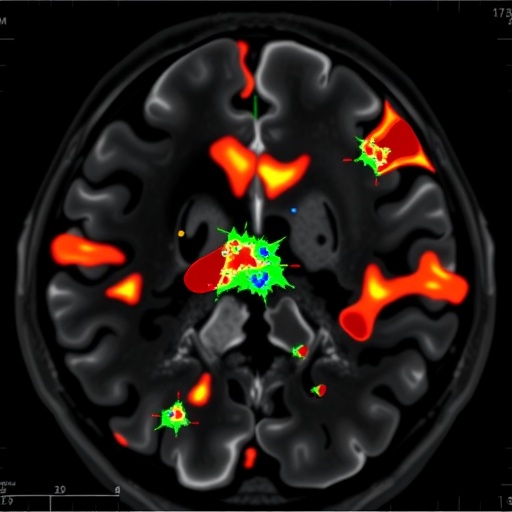

In a groundbreaking study published in the Journal of Medical Biologt Engineering, researchers have taken a significant leap forward in the automated detection and segmentation of cerebral arteriovenous malformations (AVMs) utilizing advanced Gaussian Mixture Model (GMM) clustering techniques. The significance of this research cannot be overstated, as AVMs represent a critical concern in neurovascular pathology, often leading to severe neurological deficits and considerable morbidity in affected individuals. Traditional methods of identifying and mapping these complex vascular anomalies are often labor-intensive and fraught with diagnostic inaccuracies. The innovative approach outlined by the authors, Lin, Lee, and Chen et al., promises to offer a robust alternative that enhances both efficiency and precision in clinical settings.

Cerebral AVMs, characterized by a tangle of abnormal blood vessels connecting arteries and veins, pose a substantial risk of hemorrhagic strokes. As a result, accurately identifying these lesions is fundamental to ensuring proper treatment strategies, which may involve surgical intervention or radiological therapies. The ability to segregate these pathological formations with a high degree of accuracy is imperative to reducing the incidence of misdiagnosis that can lead to devastating consequences for patients. With their study, the authors explore the efficacy of Gaussian Mixture Model clustering as a solution to the inherent challenges associated with traditional diagnostic methodologies.

Gaussian Mixture Models are probabilistic models that assume all data points are generated from a mixture of several underlying Gaussian distributions. By leveraging this statistical approach, the researchers developed an automated segmentation framework specifically geared towards magnetic resonance imaging (MRI) data. This methodology is particularly well-suited for medical imaging applications due to its ability to handle noise and variance in data effectively. As a result, implementing GMM allows for a refined analysis of the complex structures associated with AVMs in MRIs.

A comprehensive performance evaluation was conducted through metrics such as the Dice Similarity Coefficient (DSC) and Jaccard Index to quantify segmentation accuracy. Results indicated that the GMM model achieved a higher DSC than traditional methods, which is critical for clinicians who depend on accurate depictions of vascular anomalies to guide treatment decisions. These findings underscore the potential for GMM clustering to revolutionize AVM evaluation and treatment planning, positively impacting patient outcomes.